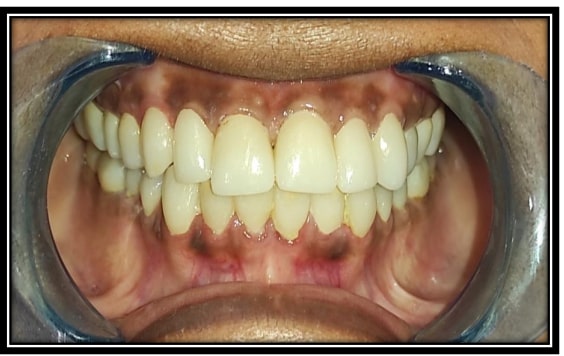

Some of Our sucessfull Smile FMR cases